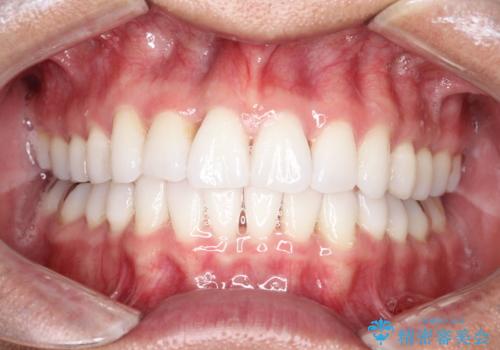

内側に入ってしまった前歯を正しい位置へ インビザライン矯正

右上の前から2番目の歯が引っ込んで、下の前歯にはガタガタがありました。

上下の歯と歯の間を少量ずつ削りスペースを作り、インビザラインにて並べる計画としました。

目立たずに矯正治療を終えることができたことに満足していただけました。